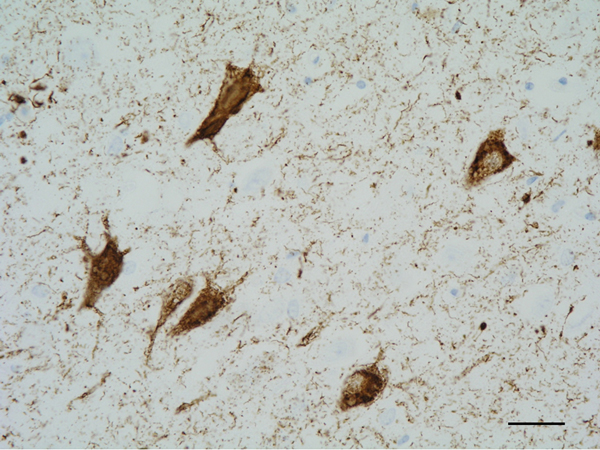

Figure 5: Neurofibrillary tangles in the CA1 region of the hippocampus. Paraffin section, AT8 immunohistochemistry, slight haematoxylin counterstaining, bar = 25μm.

The main constituent of NFTs dystrophic neurites of SPs and neuropil threads is abnormal tau (158-173) (Figures 5, 6, and 7). A combination of all six hyper-phosphorylated brain tau isoforms (3Rtau and 4Rtau expressed in brain), generated from alternative tau splicing, is characteristic of AD tau (163, 174, 175). The amount of 3Rtau is similar to 4Rtau in the human adult brain and in AD. However, possible variations in the ratio of 3Rtau/4Rtau among cell types in the human brain have not been adequately assessed. Abnormal tau in AD includes several species resulting from hyper-phosphorylation at different sites, acetylation, glycosylation, altered confor mation, truncation at glutamic acid 391 and at aspartic acid 421 (mediated by caspase 3), oligomerization, and β-sheet-rich fibril aggregation, among others (171-173, 176-196). The site of tau phosphorylation and other post-translational modifications in tau have commonalities and differences among tauopathies (197, 198). Tau inclusions in glial cells are not found in AD, unless accompanied by other tau co-morbidities including aging-related tau astrogliopathy (ARTAG) and argyrophilic grain disease (AGD) which are 4Rtau-only tauopathies.